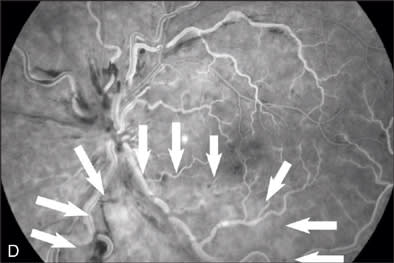

At our initial examination in August 2008, corrected visual acuity was 20/30 in the right eye and 20/50 in the left, with normal ocular pressure in both eyes. There were no rubeosis irides in either eye. Fundus examination appeared normal in the right eye while the left eye revealed a typical nonischemic CRVO (Figure 1A). Fluorescein angiography of the left eye (Figure 1B to 1E) showed generalized dilated, tortuous retinal veins, intraretinal hemorrhages, peripheral retinal non-perfusion areas, and microvascular leakage at the macula (Figure 1E, arrow). Despite the peripheral retinal ischemia, the macula itself was not ischemic at the first visit, as evidenced by the early phase FA showing 2 cilioretinal arteries supplying the fovea (Figure 1C, arrow). Spectral domain OCT (OPKO-OTI, Miami, FL.) confirmed the diagnosis of cystoid macular edema (CME). The patient got intravitreal bevacizumab (Avastin) injection (1.25 mg/0.05 mL) at the first visit.

Oximetry Analysis

Oximetry (Figure 1F) revealed multiple color alterations. In a normal eye (data not shown), the arterial oximetry appears red, venous oximetry appears blue. In this case, it appeared that the arterial oximetry appeared blue (red arrow) and the venous oximetry appeared in green (yellow arrow). An area of nerve fiber layer infarction (black arrow), corresponding to the red-free photo finding (Figure 1B) appeared white on the oximetry map (Figure 1F). The area of non-perfusion as indicated on FA (Figure 1D, arrow outlined) appeared deep blue on the oximetry map (Figure 1F).